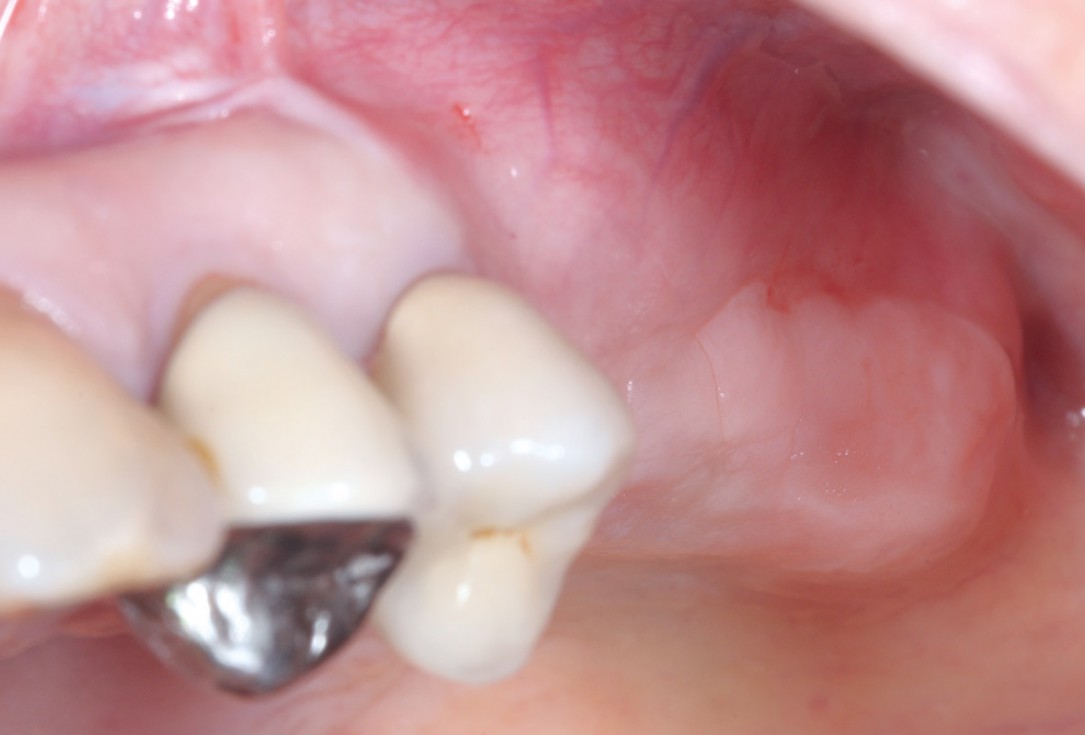

14/15 - Final prosthetic restoration- proper implant-crown ratio compared to the neighboring teethTreatment of a combined horizontal and vertical bone defect in the maxilla with maxgraft® cortico in the allogenic shell technique - Dr. R. Würdinger